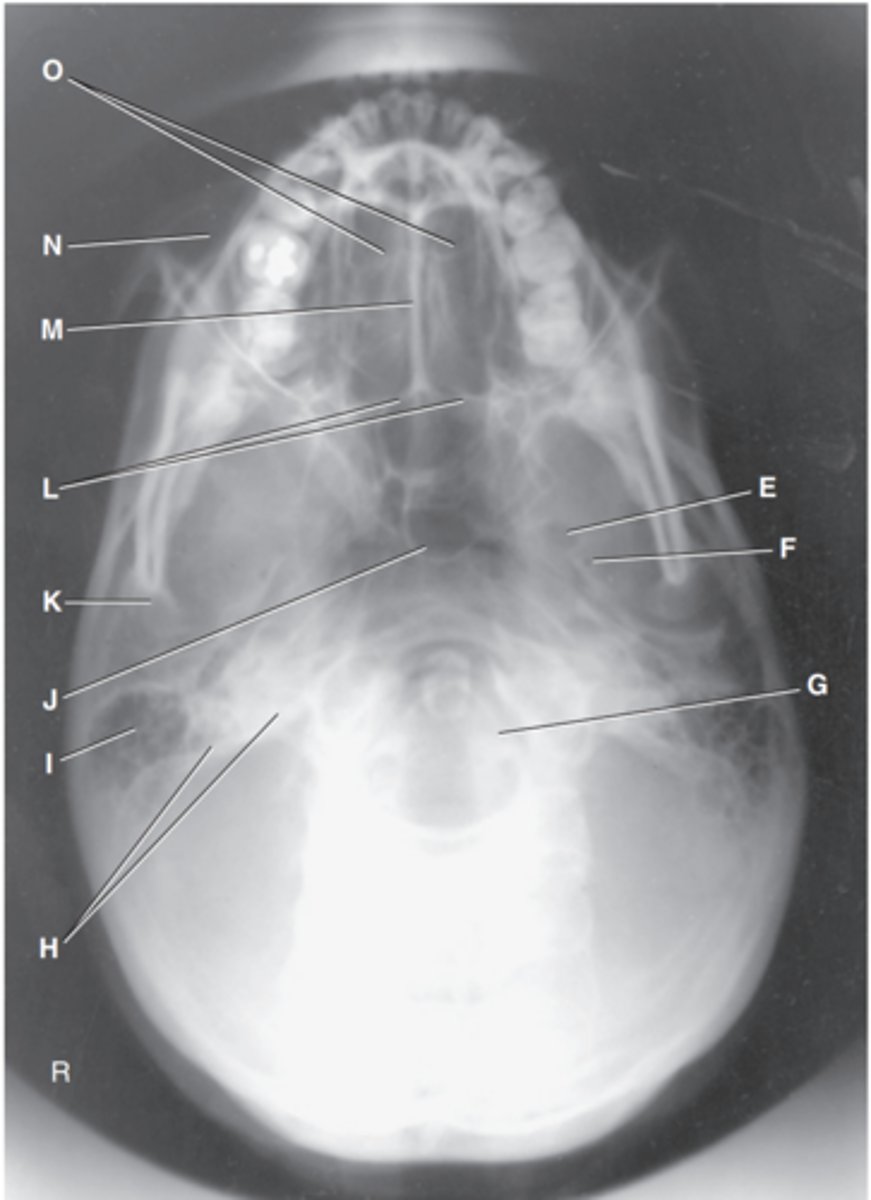

Foramen magnum

Label J

Zygomatic arch

Label A

Palatine process of maxilla

Label B

Horizontal process of palatine bone

Label C

Pterygoid hamulus of sphenoid

Label D

Foramen ovale of sphenoid

Label E

Foramen spinosum of sphenoid

Label F

Foramen magnum

Label G

Petrous pyramid of temporal bone

Label H

Mastoid portion of temporal bone

Label I

Sphenoid sinus in body of sphenoid

Label J

Condyle of mandible

Label K

Posterior border of palatine bone

Label L

Vomer

Label M